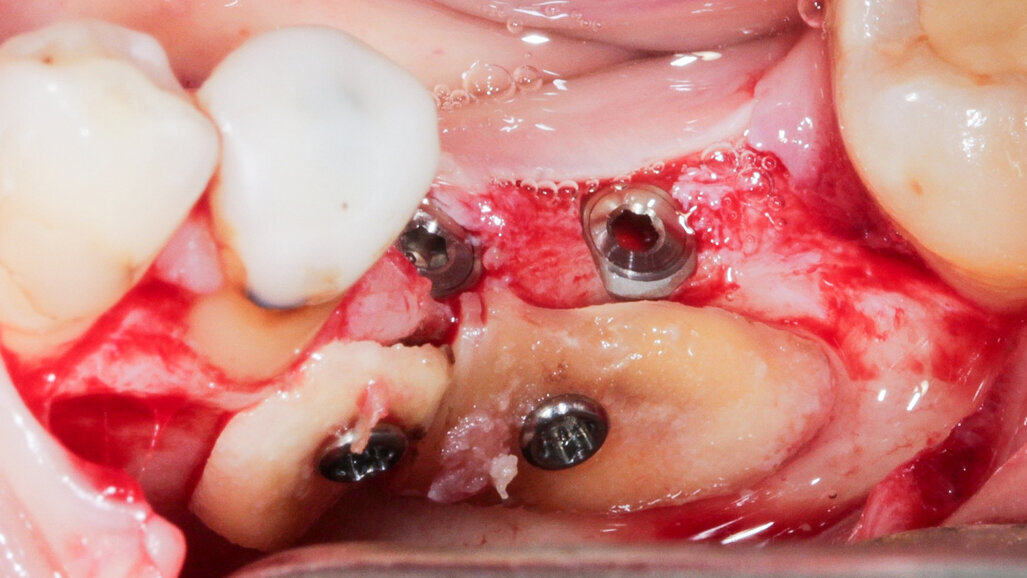

Na implantáty byly umístěny vhojovací válečky. Osteosyntetické šroubky byly odstraněny.